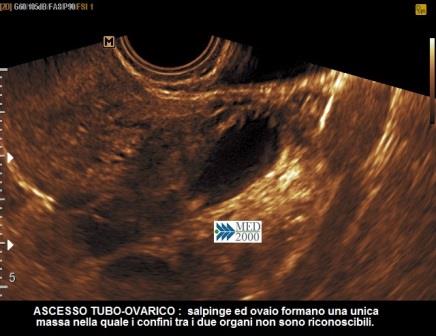

Con l'aggravarsi del processo flogistico si passa al quadro dell'ascesso tubo-ovarico in cui tuba ed ovaio sono compresi in un unica massa a contorni sfumati nella quale le strutture che la costituiscono, tuba ed ovaio, non sono più riconoscibili. Il questo caso le immagini ecografiche sono alquanto complesse: la massa relativa all'ascesso tubo-ovarico presenta dei confini sfumati, non distinguibili con le anse intestinali, e il contenuto è disomogeneo per la contemporanea presenza di aree a diversa ecostruttura (anecogene, ipoecogene, iperecogene). L'ascesso può inoltre essere circondato da liquido libero nella pelvi, in genere ad aspetto denso in quanto costituito da pus, oppure possono coesistere delle raccolte saccate a localizzazione molto varia, anche distanti dall'ascesso.